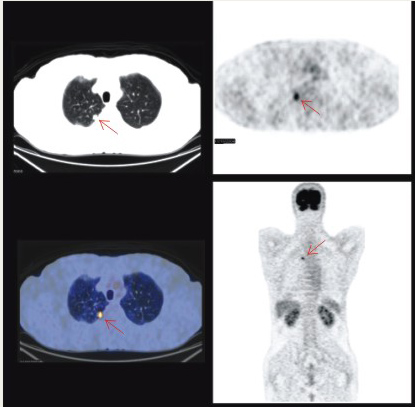

患者:男性,72歲,CT示左上肺腫塊影;PET示腫塊中向大部分壞死,周圍呈高代謝。PET-CT診斷為:左上肺癌。術(shù)后病理:鱗癌。

查體發(fā)現(xiàn)右肺上葉小肺癌,直徑0.6cm。術(shù)后病理:中分化腺癌。